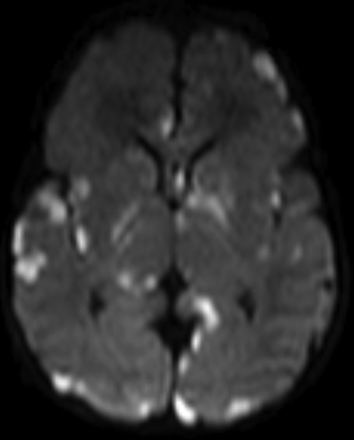

There was no statistically significant difference between groups for the duration from presentation to the date of MR imaging (10.1 versus 12.8 days, P = .08). There was a significant difference between GBS and E coli meningitis for acute development of hydrocephalus (0% versus 22%, P = .001). Ultimately, 7% (4/57) of patients with GBS meningitis required ventriculoperitoneal shunting compared with 18% (9/50) of patients with E coli meningitis (P = .14). There was a shorter mean time to development of hydrocephalus among patients with E coli meningitis compared with those with GBS meningitis (18 versus 92 days; P = .006). There was a significant difference between GBS and E coli meningitis for the development of infarct (40% versus 14%; P = .038). There was no statistically significant difference between GBS and E coli groups for leptomeningeal enhancement, cerebritis, ependymal enhancement, abscess/granuloma, subdural effusion, hemorrhage, extra-axial purulent material, intraventricular purulent material restriction, or sinus thrombosis. Representative examples of patients with GBS and E coli meningitis are seen in Figs 1 and 2.

A 12-day-old neonate with GBS meningitis. Axial DWI demonstrates multifocal areas of diffusion restriction (ADC not shown) in the parenchyma, consistent with infarcts and cerebritis.